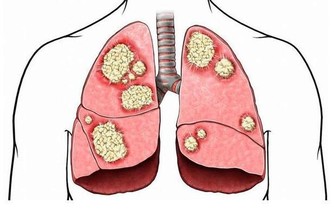

8.忽視感冒、鼻炎、咽炎

很多人耳朵感染炎症都是上呼吸道疾病引起的,特別是鼻炎、咽喉炎、感冒等都會引起中耳炎等耳部感染。

耳部的炎症通常都是繼發於鼻炎、咽炎等上呼吸道感染之後炎症波及咽鼓管,

或是鼓膜有破損後感染造成的,故應及時治療,以防聽力損害。